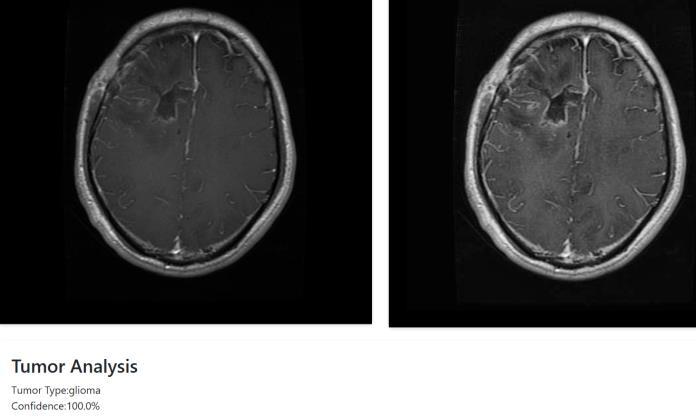

Theproposedsystemarchitectureconsistsoftwointegrated modulesdesignedtoenhancethediagnosisofbraintumors. Thefirstmoduleusesadeeplearningmodel,specificallya DNN algorithm, to classify MRI brain images into four categories: glioma, meningioma, pituitary tumor, or no

tumor. It extracts features from the images and uses a Softmax layer to predict the tumor type accurately. Once classified, the second module takes over to estimate the tumor'sdepthbyreconstructinga3Dmodelfrom2DMRI slices.UsingsegmentationtechniquesfromSimpleITK,the tumor region is isolated and passed to VTK for 3D visualization. These slices are then stacked to build a volumetricimageofthetumor.Thesystemcalculatesdepth by measuring the distance from the brain surface to the tumor's deepest point. This helps provide spatial context, supportingbettersurgicalplanning.

The proposed system is implemented using a supervised DeepNeuralNetwork(DNN),designedtoeffectivelyclassify brain tumors based on MRI images. The DNN processes image data to learn complex patterns that distinguish betweenvarioustumortypesandnormalbrainconditions. Forimagepreprocessingandenhancement,theframework incorporates OpenCV, which optimizes image clarity and speedsupprocessing.Inadditiontoclassification,thesystem utilizesVTKandSimpleITKlibrariesfor3Dreconstructionof the tumor, enabling accurate depth value estimation by generating a volumetric model from 2D slices. This integrationallowsthesystemnotonlytodetectthepresence of a tumor but also to provide insights into its spatial dimensions within the brain. The model was trained on a comprehensive dataset and achieved a confidence level of 99.8% in correctly classifying tumor types. This high accuracy,combinedwithprecisedepthanalysis,makesthe dual-module system a robust tool for both diagnostic and surgicalplanningpurposes.

Thisstudypresentsadual-modulesystemthateffectively combinesdeeplearningwithmedicalimagereconstruction toimprovebraintumordetectionandanalysis.UsingaDeep Neural Network (DNN), the system accurately classifies brainMRIimagesintovarioustumortypes,achievingahigh confidence level of 99.8%. Alongside classification, the integrationofVTKandSimpleITKenablesthegenerationof 3Dtumormodels,whichhelpin estimatingthedepthand spatial position of the tumor within the brain. This depth analysis is valuable for understanding tumor severity and guidingtreatmentdecisions.Byworkingwithactualmedical imagedata,thesystemoffersbothdiagnosticaccuracyand clinicalrelevance.Itsimplifiestheworkflowforradiologists byprovidingbothatumortypepredictionandavisual3D referenceinonesystem.Althoughtheresultsarepromising, further improvements could make the model more adaptable to a wider range of cases and patient data. The projectdemonstrateshowcombiningmachinelearningwith 3Dimagingtoolscanbringrealvaluetomedicaldiagnostics. Withmoredataandcontinuedrefinement,thisapproachcan support doctors in early diagnosis, better treatment planning, and improved patient outcomes in brain tumor care.